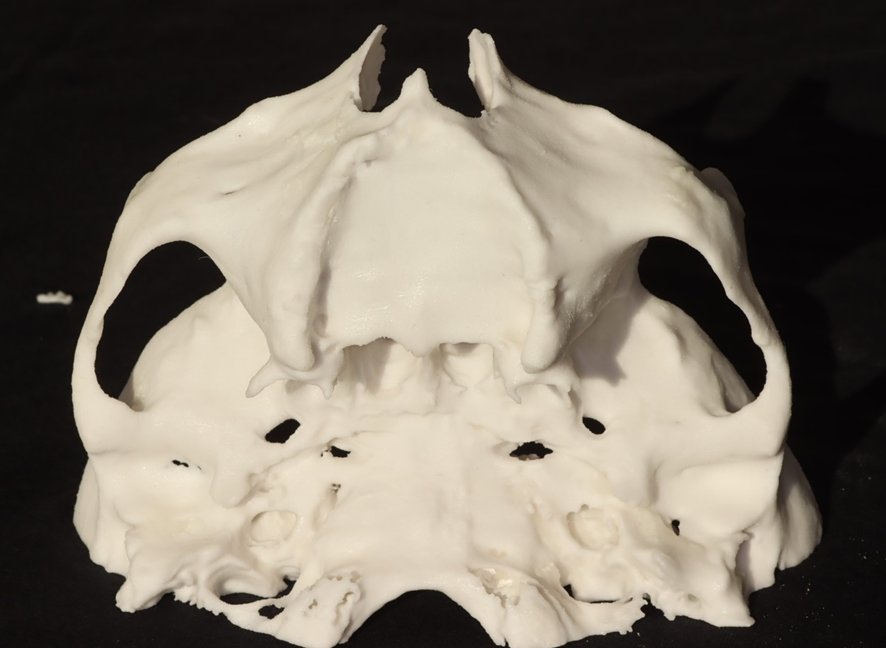

3- Impressão de prototipagem;

4- Análise do biotipo facial: dolicofacial (zigoma com pequeno volume), braquifacial (zigoma com grande volume) e mesofacial (zigoma proporcional em volume);

5- Análise da altura do rebordo alveolar remanescente. Dependendo da altura do remanescente, a angulação da entrada no zigoma poderá ser alterada com risco de trepanação. Requer do cirurgião-dentista destreza para correção da fresagem;

6- Análise da espinha nasal. Dependendo da sua anatomia, haverá necessidade de osteotomia para corrigir a angulação de entrada no zigoma. Requer do cirurgião-dentista habilidade para a correção da fresagem e para evitar a trepanação;

7- Simulação da instalação dos Pilares Z em biomodelo. Facilita a instalação durante o procedimento cirúrgico, altura, inclinação, local de osteotomia; quando necessário, posição da plataforma do implante, acomodação do implante no nicho da osteotomia